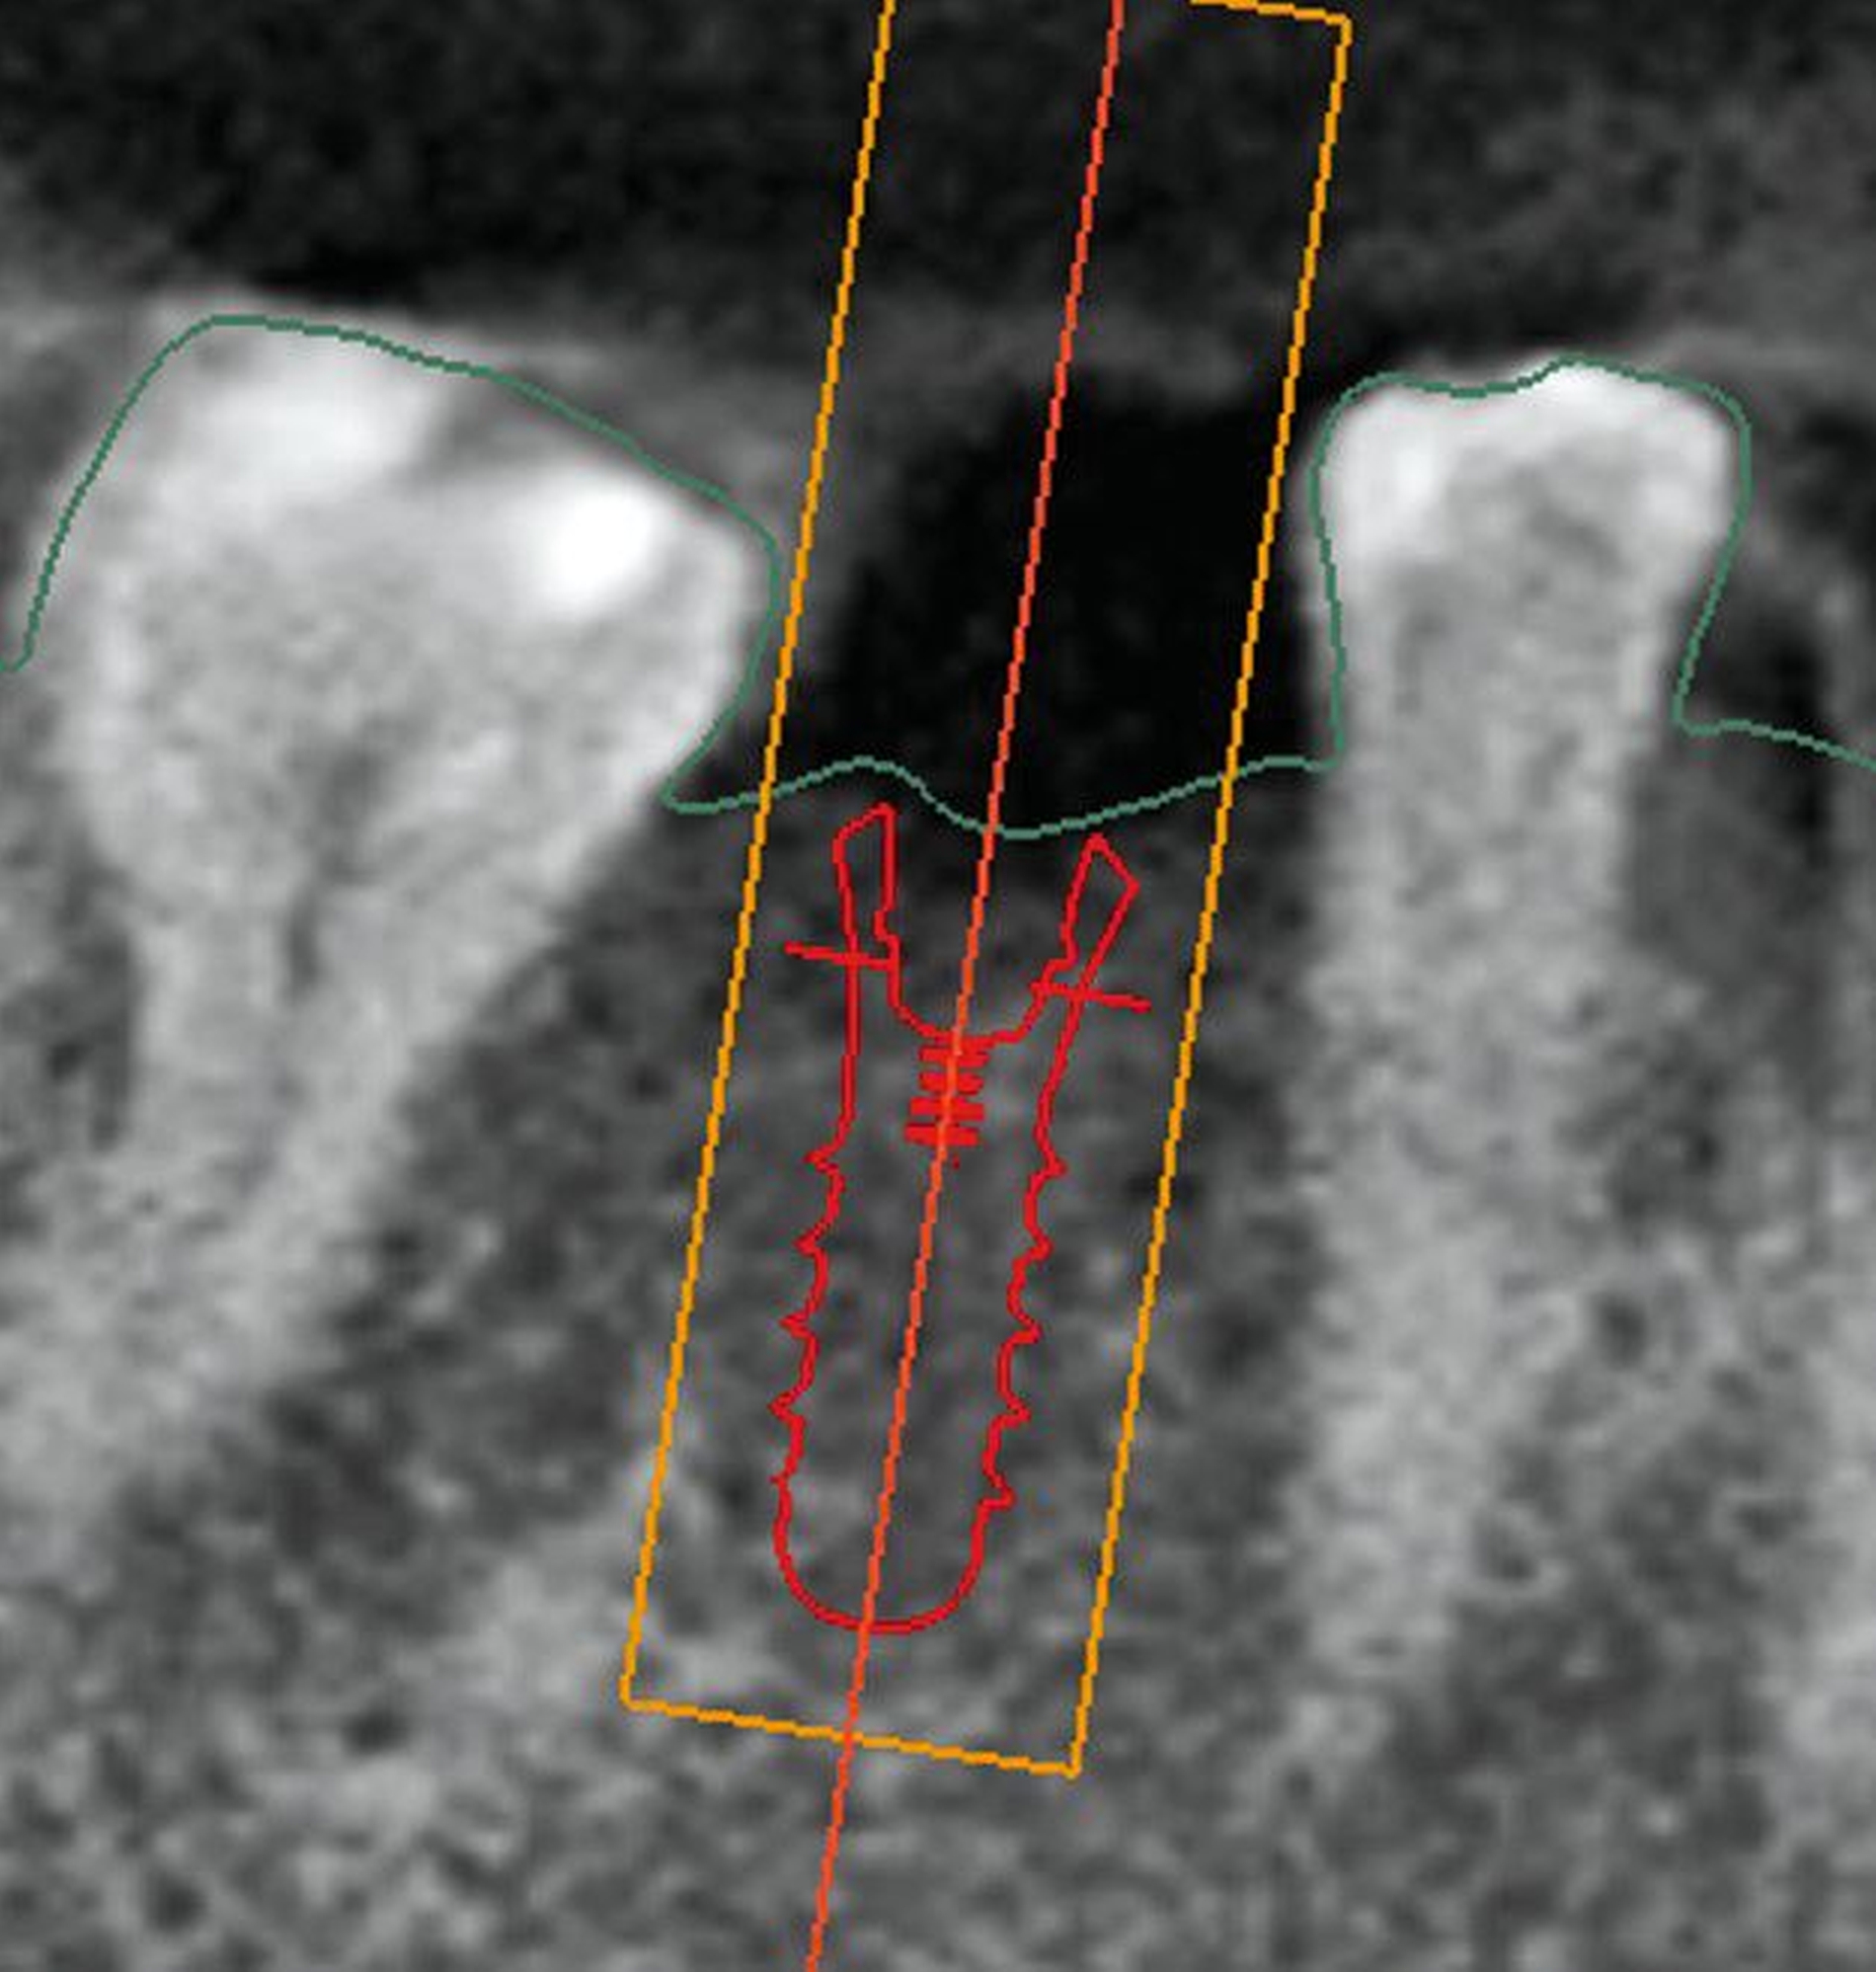

Nach der Beurteilung der chirurgischen Risiken werden die prothetischen Voraussetzungen evaluiert. Ist ausreichend Platz für die Idealgestaltung der zukünftigen Restauration vorhanden (sowohl was die Anatomie als auch was die funktionelle Gestaltung angeht), stellt dies die S-Variante dar. Im vorliegenden Fall zeigt sich der Zahn 47 kariös sowie teilweise rotiert und mesioincliniert, wodurch der prothetische Raum für 46 partiell verschlossen ist (Abbildung 2). Wir entschieden uns daher für eine simultane Versorgung von Zahn 47 mit einer Teilkrone. Ziel war es, die Insertionsachse der Implantatkrone und die Reinigbarkeit der Interdentalräume zu optimieren (Abbildung 3).